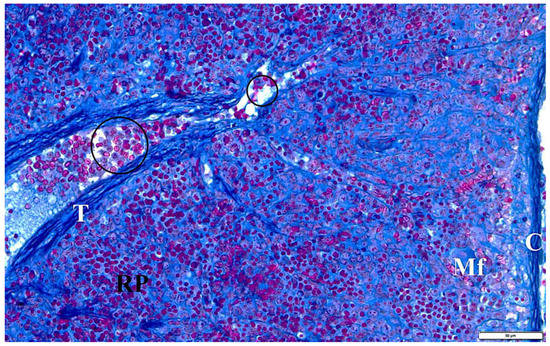

Figure 9.

The spleen of a rat with transplacental infection with B. microti 3 weeks after birth. C—fibrous capsule, Mf—macrophage, RP—red pulp, T—trabecula with a trabecular vessel, circular markings—longitudinal sections through trabecular vessels with multicolored erythrocytes and congestive changes.

In the presented studies, in the histological structure of the spleen of intrauterine infected rats with B. microti, no clear deviations from the normal architecture of the organ were observed, appropriate to the young age of the observed individuals. Both white and red pulp were visible. However, the line between them was blurred (Figure 8). The lymphoid follicles were irregular in shape and the marginal layer was barely perceptible. The fibrous capsule of the spleen of rats under physiological conditions is characterized by a small amount of connective tissue. In the observed preparations of spleen sections taken from rats with congenital babesiosis, a small amount of it was visible with the presence of mesothelial cells covering its surface. The connective tissue capsule detached from the parenchyma of the organ in places, creating fissured spaces. These dissections indicate degenerative changes, possibly associated with edema. The trabeculae extending from the splenic capsule were visible and contained vessels with fibrin-precipitated hyperemia and numerous blood cells adhering to the endothelial wall (Figure 9). In addition, a characteristic feature was the differentiation of erythrocytes.

Using high magnification, the presence of intracellular inclusions in the red pulp could be seen, which, based on the structure, can be defined as invasive forms of B. microti. In some preparations, mitotic cell divisions were also observed, which are a manifestation of repair and regeneration processes or, at this stage of development, still in the residual phase of erythropoiesis. Voids were observed in many areas, indicating atrophic retrograde changes, as well as macrophages responsible for the phagocytosis of disintegrating erythrocytes and B. microti protozoa (Figure 10).